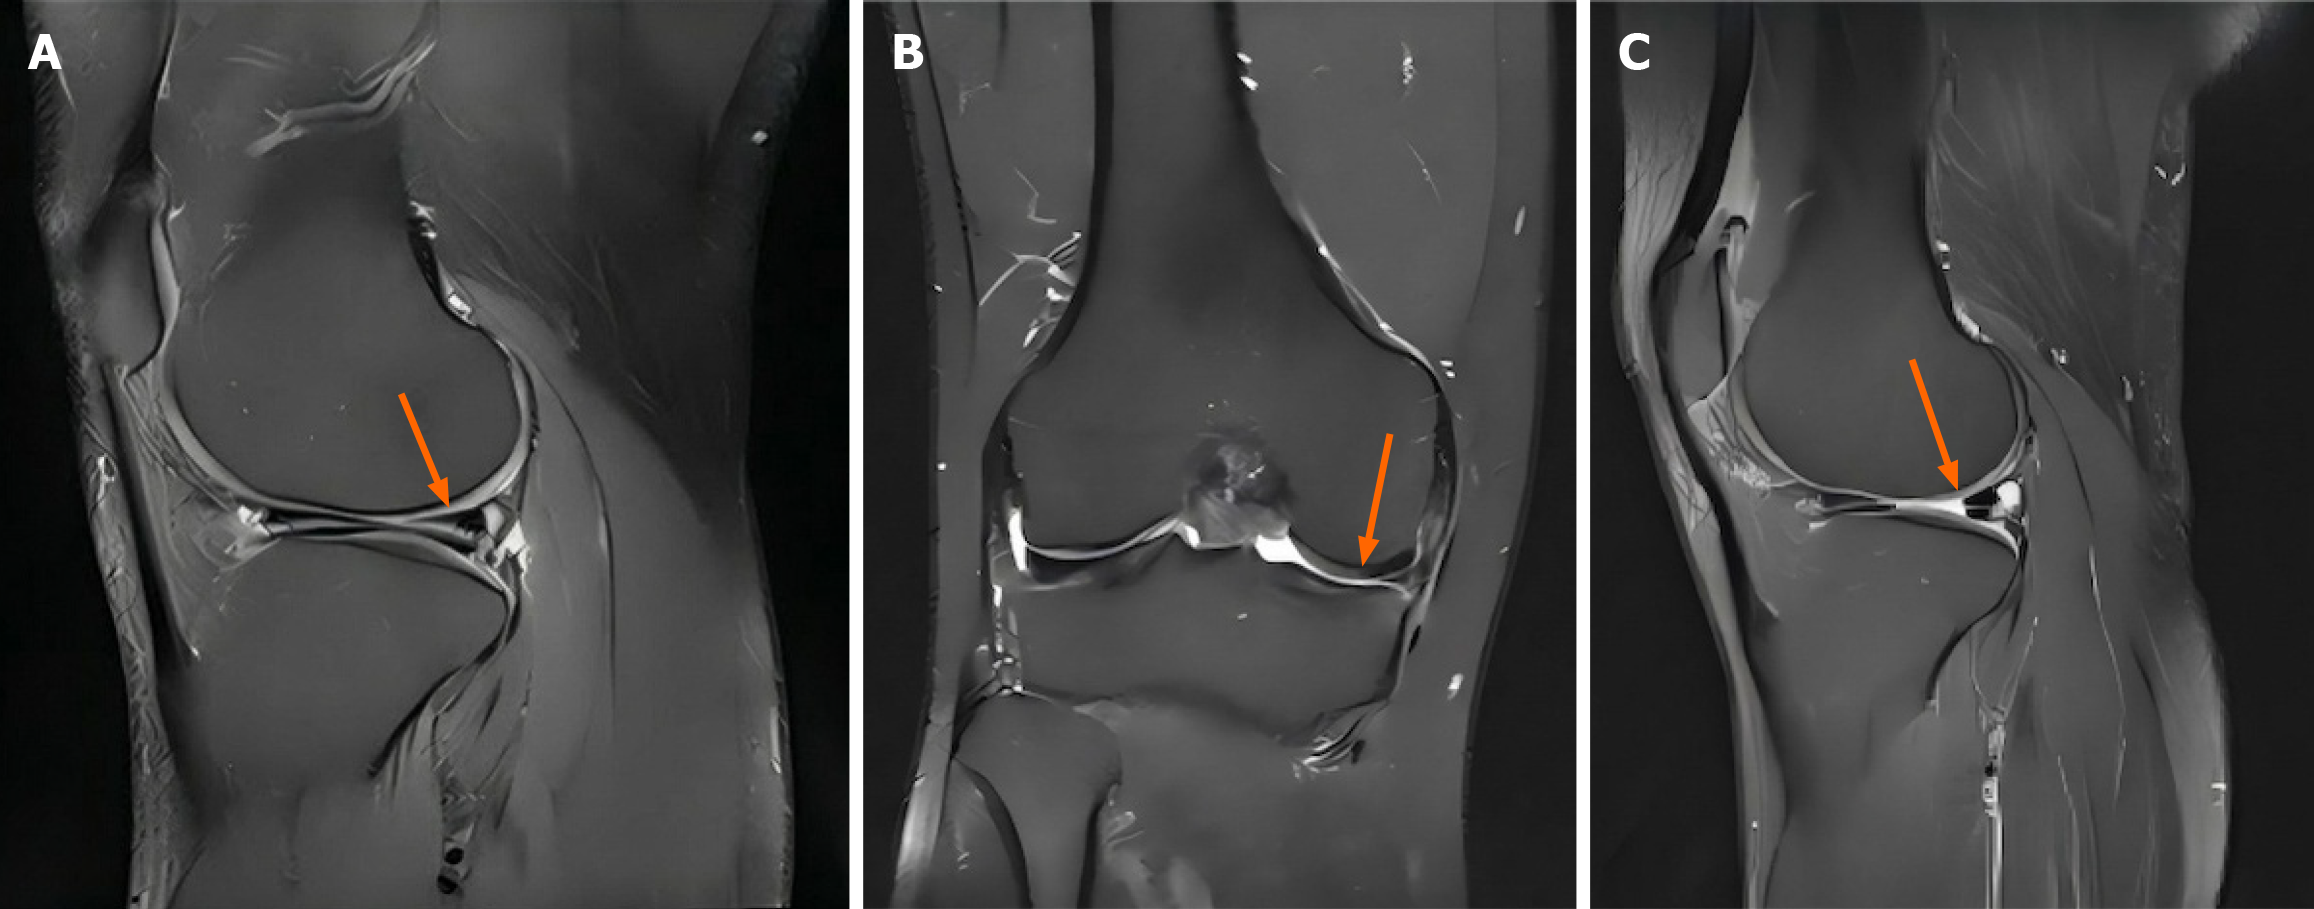

A:治疗前矢状位T2加权像显示内侧半月板后角高信号强度(箭头),提示III级退行性改变;B:治疗前冠状位T2加权像显示内侧半月板实质内信号异常(箭头);C:治疗后(12个月)矢状位T2加权像显示后角信号强度降低(箭头)且组织均匀性改善。

定量T2映射显示,整个半月板平均T2弛豫时间从基线38.5±4.2毫秒降至6个月时的34.8±3.9毫秒和12个月时的31.2±3.8毫秒(均P<0.001),表明胶原结构增强、水分含量降低(表2,图2)。后角改善最为显著(从41.2±5.1毫秒降至32.5±4.2毫秒)。形态学评估中,63.2%的患者半月板信号强度增强,40.8%的患者信号异常完全消退。最初存在的半月板挤出(平均3.8±1.2mm)在12个月时减少至2.9±1.0mm(P=0.003),其中35.3%的患者挤出量降至3mm以下。随访期间未见原有撕裂进展或新发撕裂。